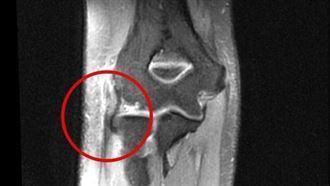

罹「網球肘」 竟害老司機差點翻車

別小看「網球肘」!竟差點讓司機「車輛打滑」釀禍,一名...